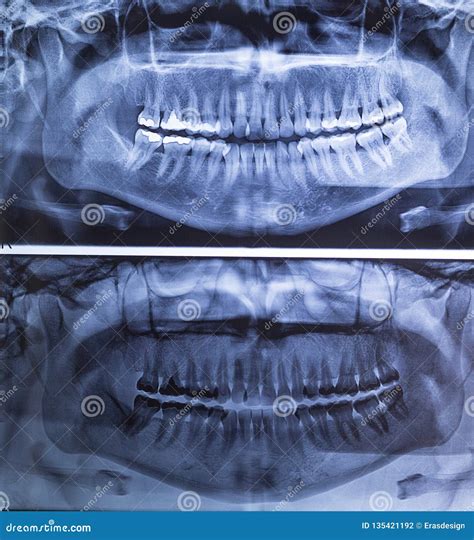

When you visit a dentist for a comprehensive oral health assessment, you might be asked to undergo a Panoramic Teeth X Ray. This specialized imaging technique is a cornerstone of modern dentistry, providing clinicians with a single, expansive view of your entire mouth. Unlike standard bitewing or periapical X-rays that focus on one or two teeth, a panoramic image captures the upper and lower jaws, the temporomandibular joints (TMJ), the nasal area, and all the teeth in one comprehensive capture. Understanding why this procedure is necessary and how it works can help alleviate any concerns you may have during your next dental examination.

The process of getting a Panoramic Teeth X Ray is fast, painless, and non-invasive. You do not need any special preparation before the appointment. The procedure typically takes less than a minute to complete.

Once the images are generated, your dentist will examine them for any abnormalities. Because the image is an orthopantomogram, it flattens the curved jaw into a two-dimensional plane. This allows the dentist to compare the symmetry of the left and right sides of your mouth. They will look for: